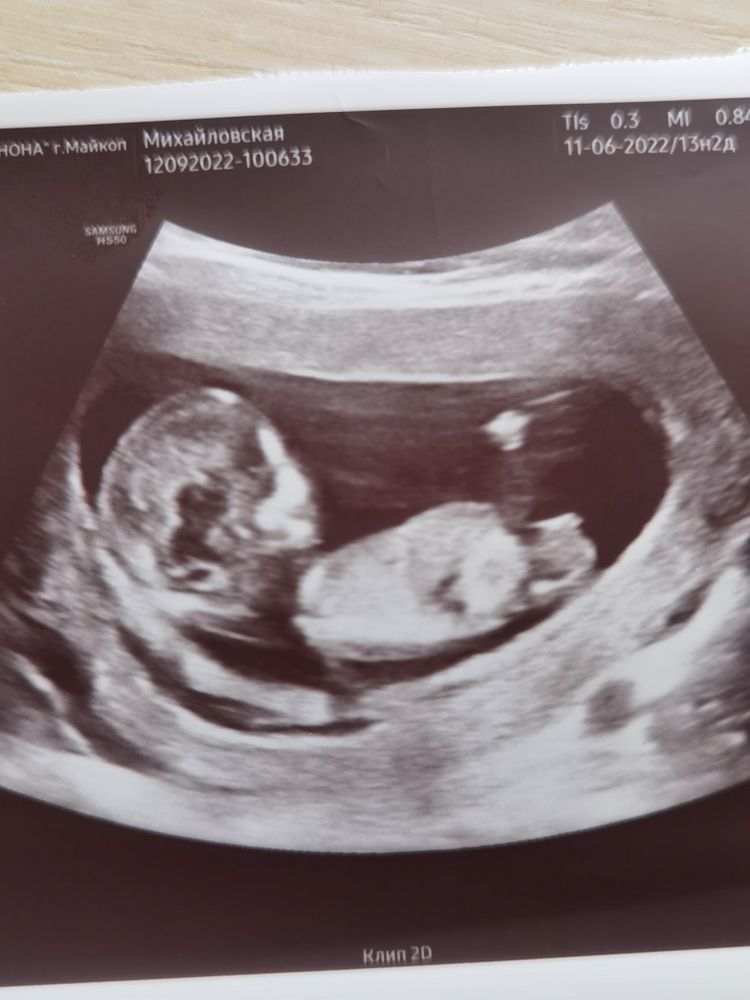

Зачем делают скрининг в 12 недель беременности

Зачем делают скрининг в 12 недель беременности 118 фото